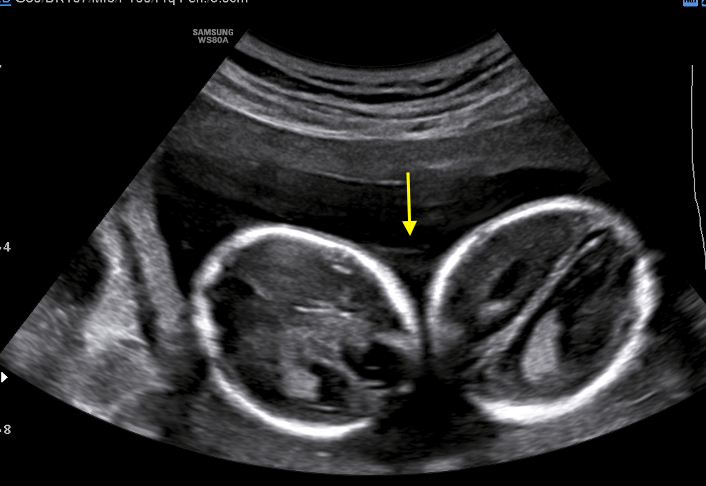

A healthy 39-year-old woman G4P3 was admitted to our high-risk pregnancy outpatient service due to a MC-DA twin pregnancy. Monochorionicity was suspected by the referring gynecologist during the dating ultrasound scan (US). The nuchal translucency US at the 12th week of gestation highlighted a “T” sign of the dividing membrane with a unique anterior placenta confirming a MC-DA twin pregnancy, as shown in Fig. 1. Soft markers for trisomy were found to be normal for both twins. The US performed during the 14th week of gestation showed the twins significantly closer to each-other standing on the same side of a free-floating thin membrane inserted on the placenta. This image raised the suspicion for a spontaneous septostomy (Fig. 2). The patient underwent amniocentesis as the combined serum screen showed an increased risk for Trisomy 21. US assisted invasive procedure did not detect the dividing membrane deposing for a PMM twin pregnancy following SS. A single sample of amniotic fluid was obtained and tested normal for fetal karyotype (46, XX). According to International Guidelines US imaging was performed every two weeks. Anomaly scan was normal and all subsequent Doppler US showed a normal twin growth and fetal wellbeing until the early third trimester [14, 15, 16]. The US performed at the 27th week of gestation showed a strict contiguity of the umbilical cords with a suspicion for cord entanglement on 3-dimensional (3D) US (Fig. 3A,B). The patient was hospitalized for close pregnancy surveillance. Fetal heart monitoring and US scan were daily performed. Steroids were administered for prevention of respiratory distress syndrome. The 29th week US scan highlighted a growth discordance ranging around 21% (symmetric growth at the 71° centile (estimated weight: 1328 gr) and at the 36° centile (estimated weight: 1043 gr) for Twin A and Twin B respectively). An episode of prolonged bradycardia was registered for Twin A. An emergency cesarean section was performed: two healthy girls were born (Twin A: weight 1360 gr, Apgar 4 and 7 at 1st and 5th minute respectively — Twin B: weight 1000 gr, Apgar 8 and 9 at 1st and 5th minute respectively). Cord entanglement was confirmed as shown in Fig. 4. The mother’s postoperative recovery was uneventful. Twins’ developmental follow-up at 12 months of age was normal.

Fig. 3.Sonograms depicting 3-dimensional imaging of cord entanglement suspected during the 27th week US.